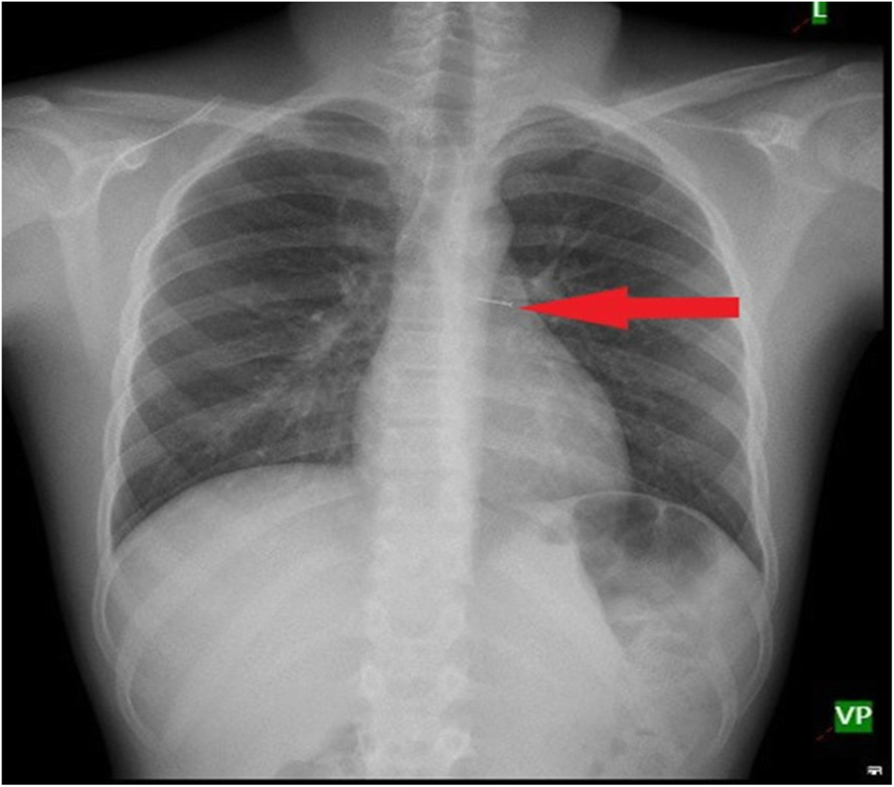

Fig. 6From: Clinical variables responsible for early and late diagnosis of foreign body aspiration in pediatrics age groupChest x-ray showing pin in the left main bronchusBack to article page